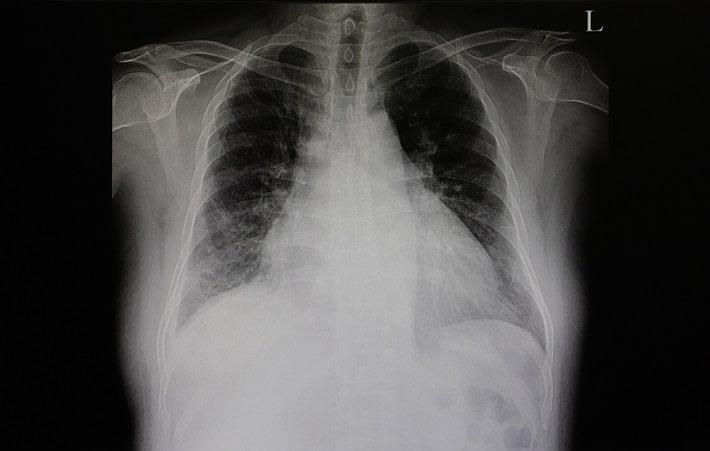

אבחון ובדיקות